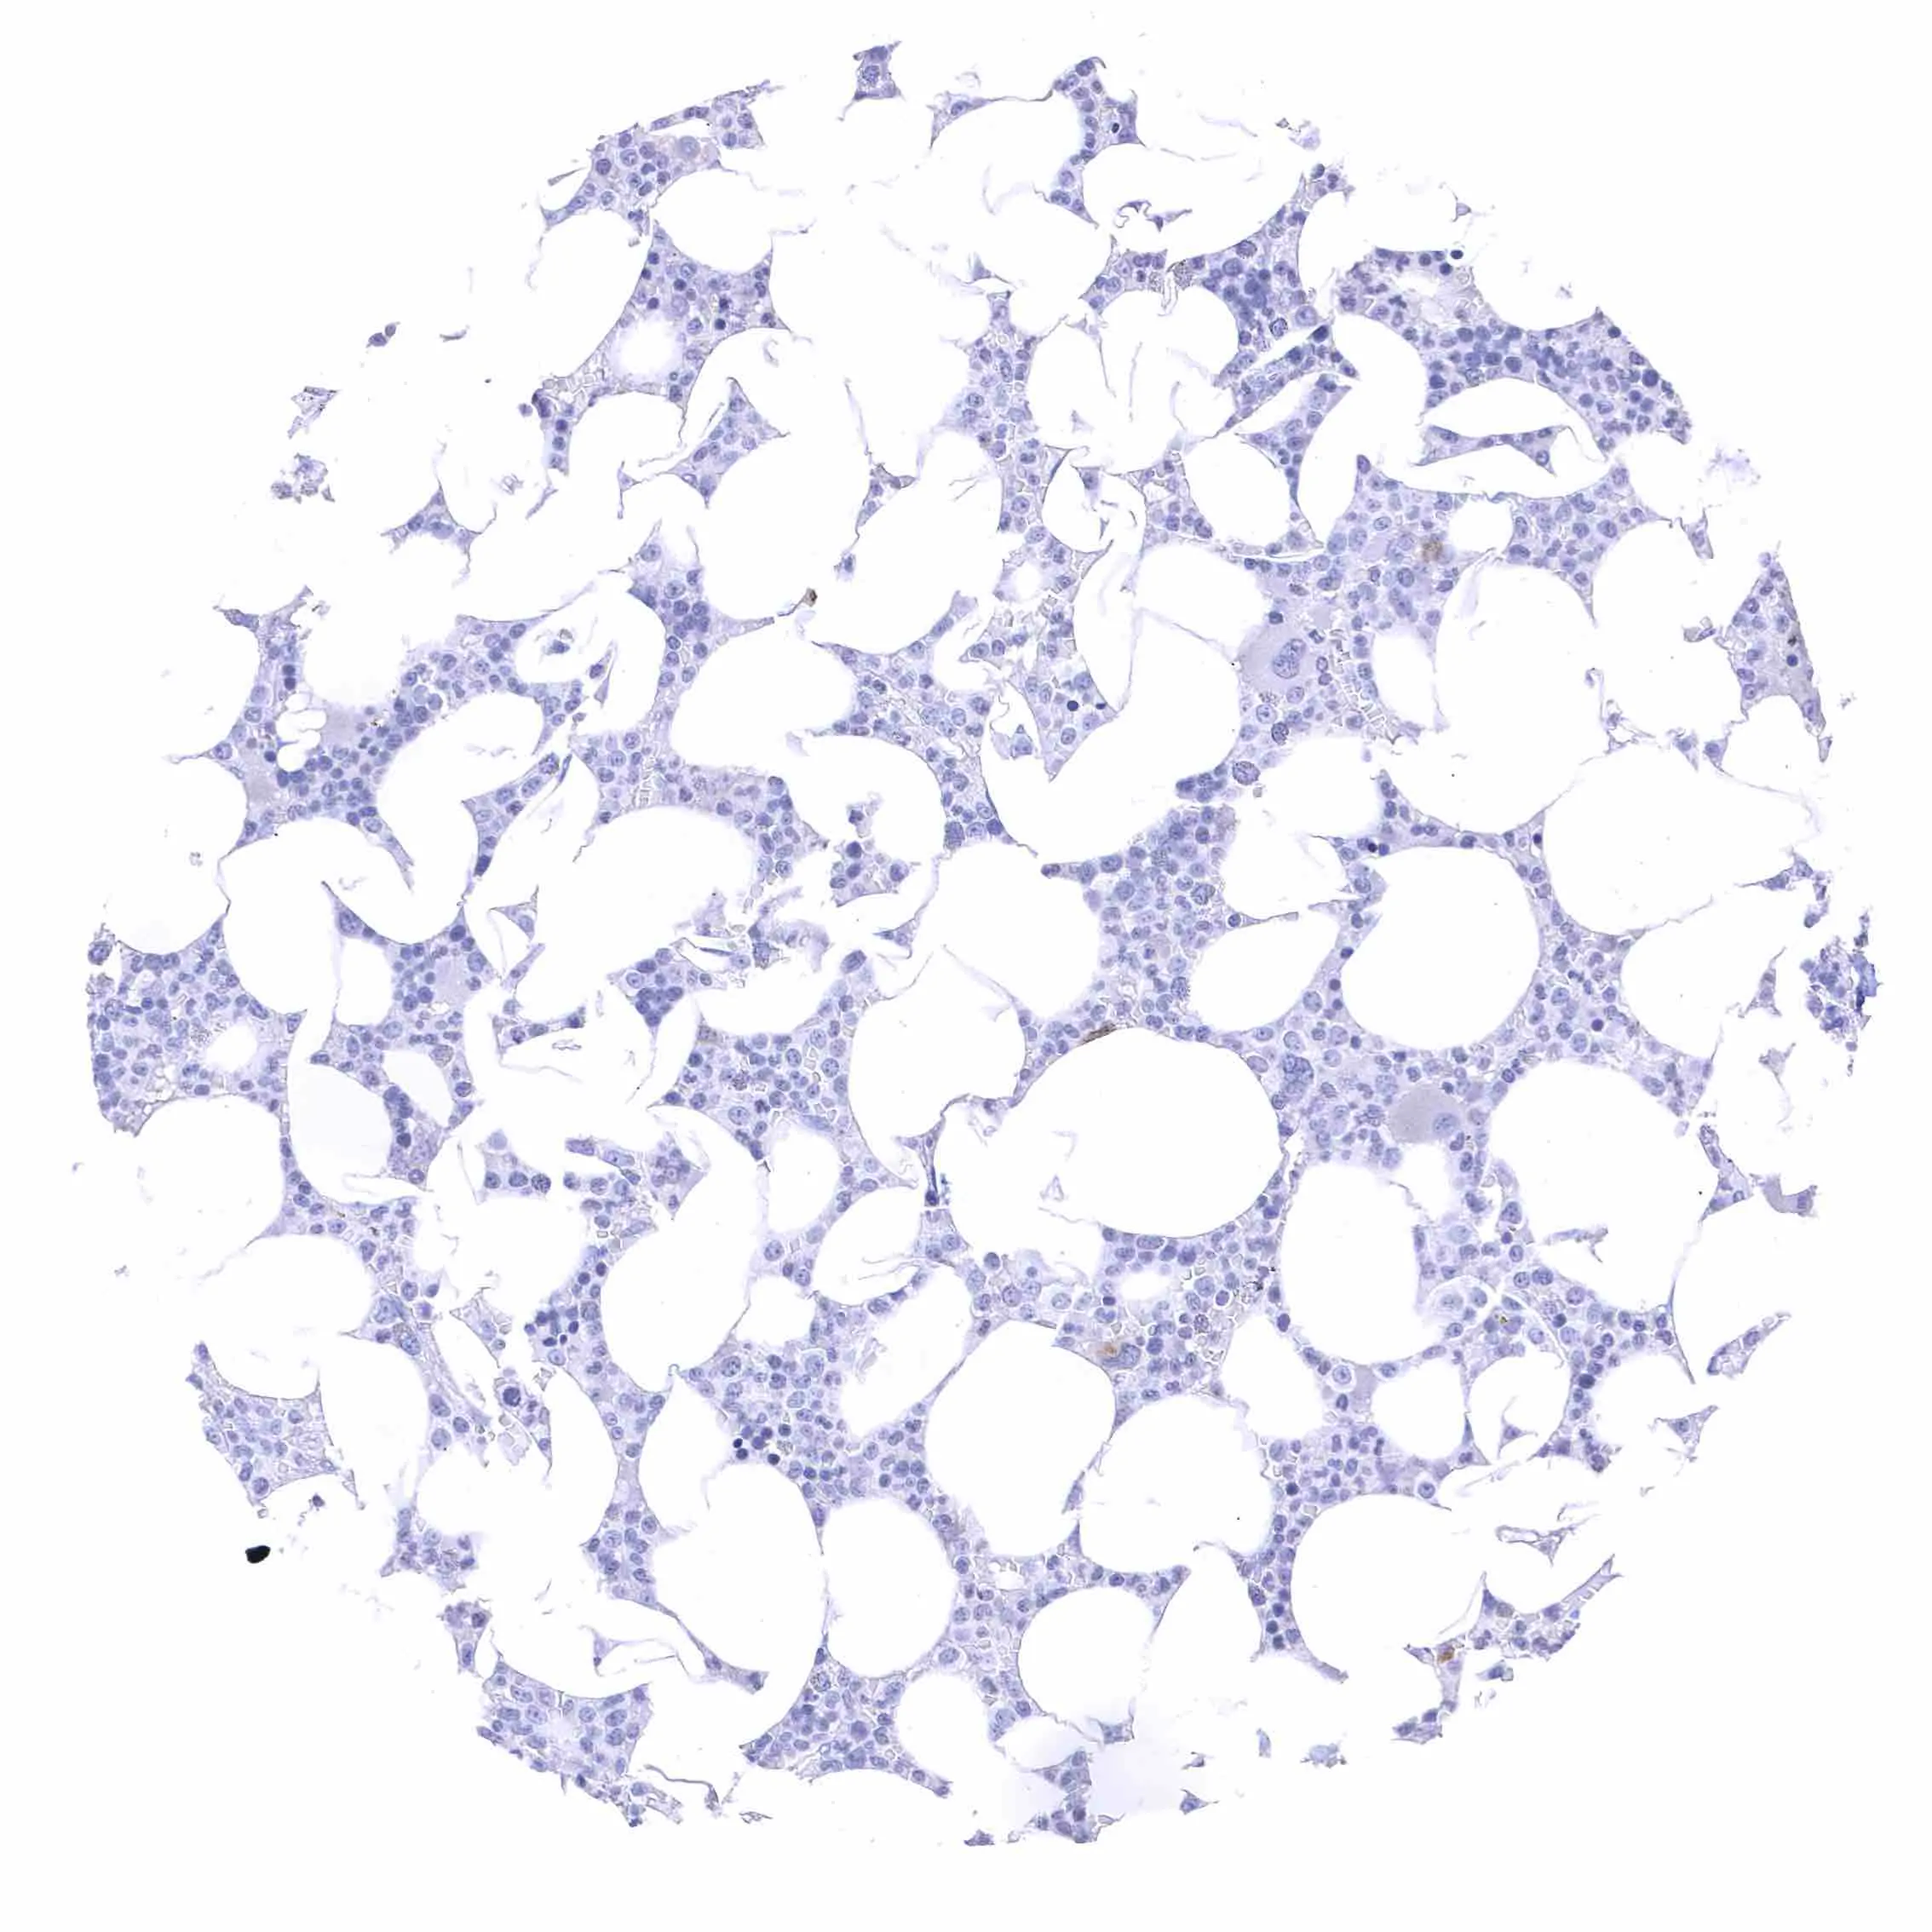

Fat